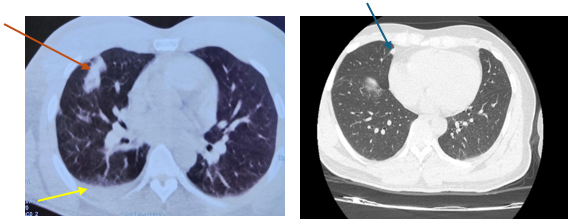

Đến 6 tháng sau bệnh nhân đi khám sức khoẻ được chụp cắt lớp vi tính lồng ngực cho kết quả:Vài nốt đặc thùy giữa và dưới phổi phải, nốt lớn kích thước 10x25mm, tràn dịch màng phổi phải => vào Trung tâm Y học hạt nhân và Ung bướu đánh giá và điều trị

Hình 1: Hình ảnh  cắt lớp vi tính lồng ngực: nốt tổn thương u phổi phải kích thước 10x25mm (mũi tên đỏ), dịch màng phổi phải (mũi tên vàng), tổn thương di căn phổi (mũi tên xanh).